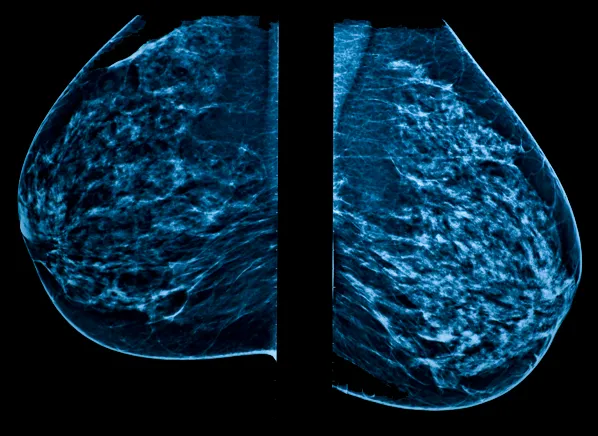

Yet this clearly cautious group concluded that about 2800 breast cancer cases a year in the US stem from medical radiation. This is an astounding number to me, a lot of women! Radiation Research spokeswoman Dr. Rebecca Smith-Bindman acknowledges that “they can potentially be reduced.” Radiologists have been telling me for thirty years that mammograms are completely safe, but that just in case, the new mammograms will be lowering the radiation dose for folks like me who worry about such things.

But a mammogram? No, thank you.